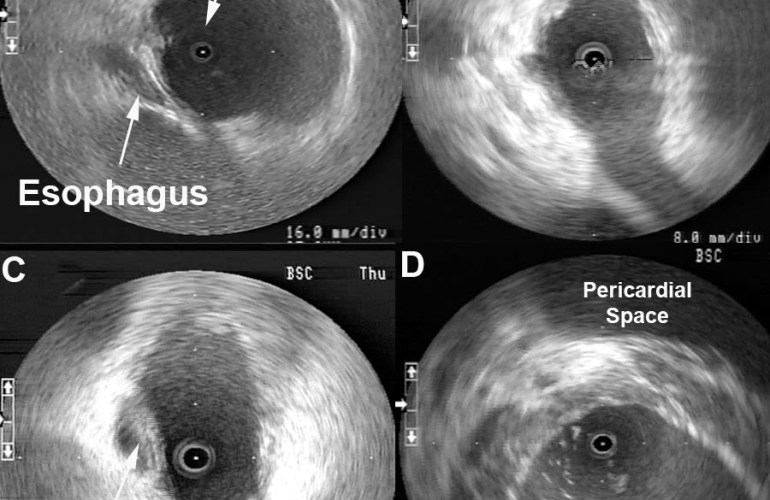

Esophageal Proximity can be monitored to guide locations of ablation to help minimize risk of esophageal damage. The entire length of esophagus that is contiguous with the left atrial posterior wall can be visualized with intra left atrial ICE to monitor ablation delivery and power titration. [1] Figure 1A shows the typical location of the esophagus during an atrial fibrillation ablation. Ablation over the esophagus is avoided or power is titrated to minimize risk of esophageal damage. Endocardial thrombi or coagulum can be detected using radial ICE as shown in Figure 1B. Left atrial damage can also be monitored using radial ICE. Figure 1C shows an unusual case of a tear or rent in the endocardium discovered during an atrial fibrillation ablation. Finally, though radial ICE is not the ideal imaging modality to evaluate for pericardial effusions given its limited far-field resolution. Figure 1D shows the pericardial space in view when an intra-left ventricular ICE position is utilized.

Figure 1 Radial ICE to Monitor for Intraprocedural Complications. Image A shows the left pulmonary vestibule with catheter evident at 9 o’clock and the esophagus viewed obliquely at ~7 o’clock. Image B shows a coagulum versus thrombus adherent to the endocardium. Image C shows a left atrial endocardial tear that did not result in pericardial effusion. Image D shows the pericardial space when ICE catheter positioned across the mitral annulus in the LV.